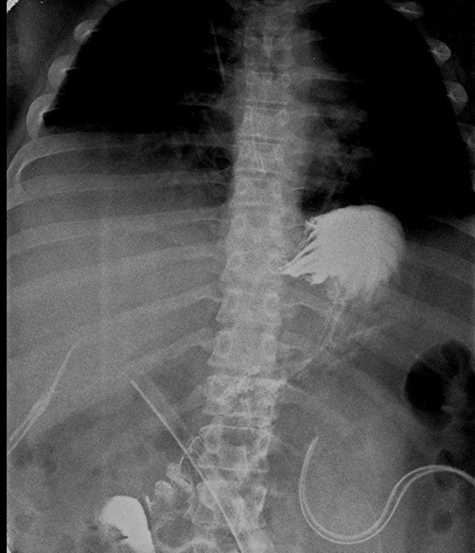

A follow-up esophagogastroduodenal series performed five days later demonstrated appropriate contrast passage without evidence of leakage or delayed gastric emptying (Figure 4). Enteral diet was reintroduced seven days after drain manipulation and repositioning. Management of the low-output fistula included continued parenteral nutrition and administration of octreotide. The Blake drain was removed after output decreased significantly. After discharge, the patient remained immobile at home, consistent with his prior lifestyle, which, according to the family’s report by phone, may have contributed to what appeared to be a pulmonary embolism; however, no clinical evidence is available to support this. The patient subsequently died at home one week later.

Figure 4: Esophagogastroduodenal series after tube repositioning: there was adequate passage of contrast material.